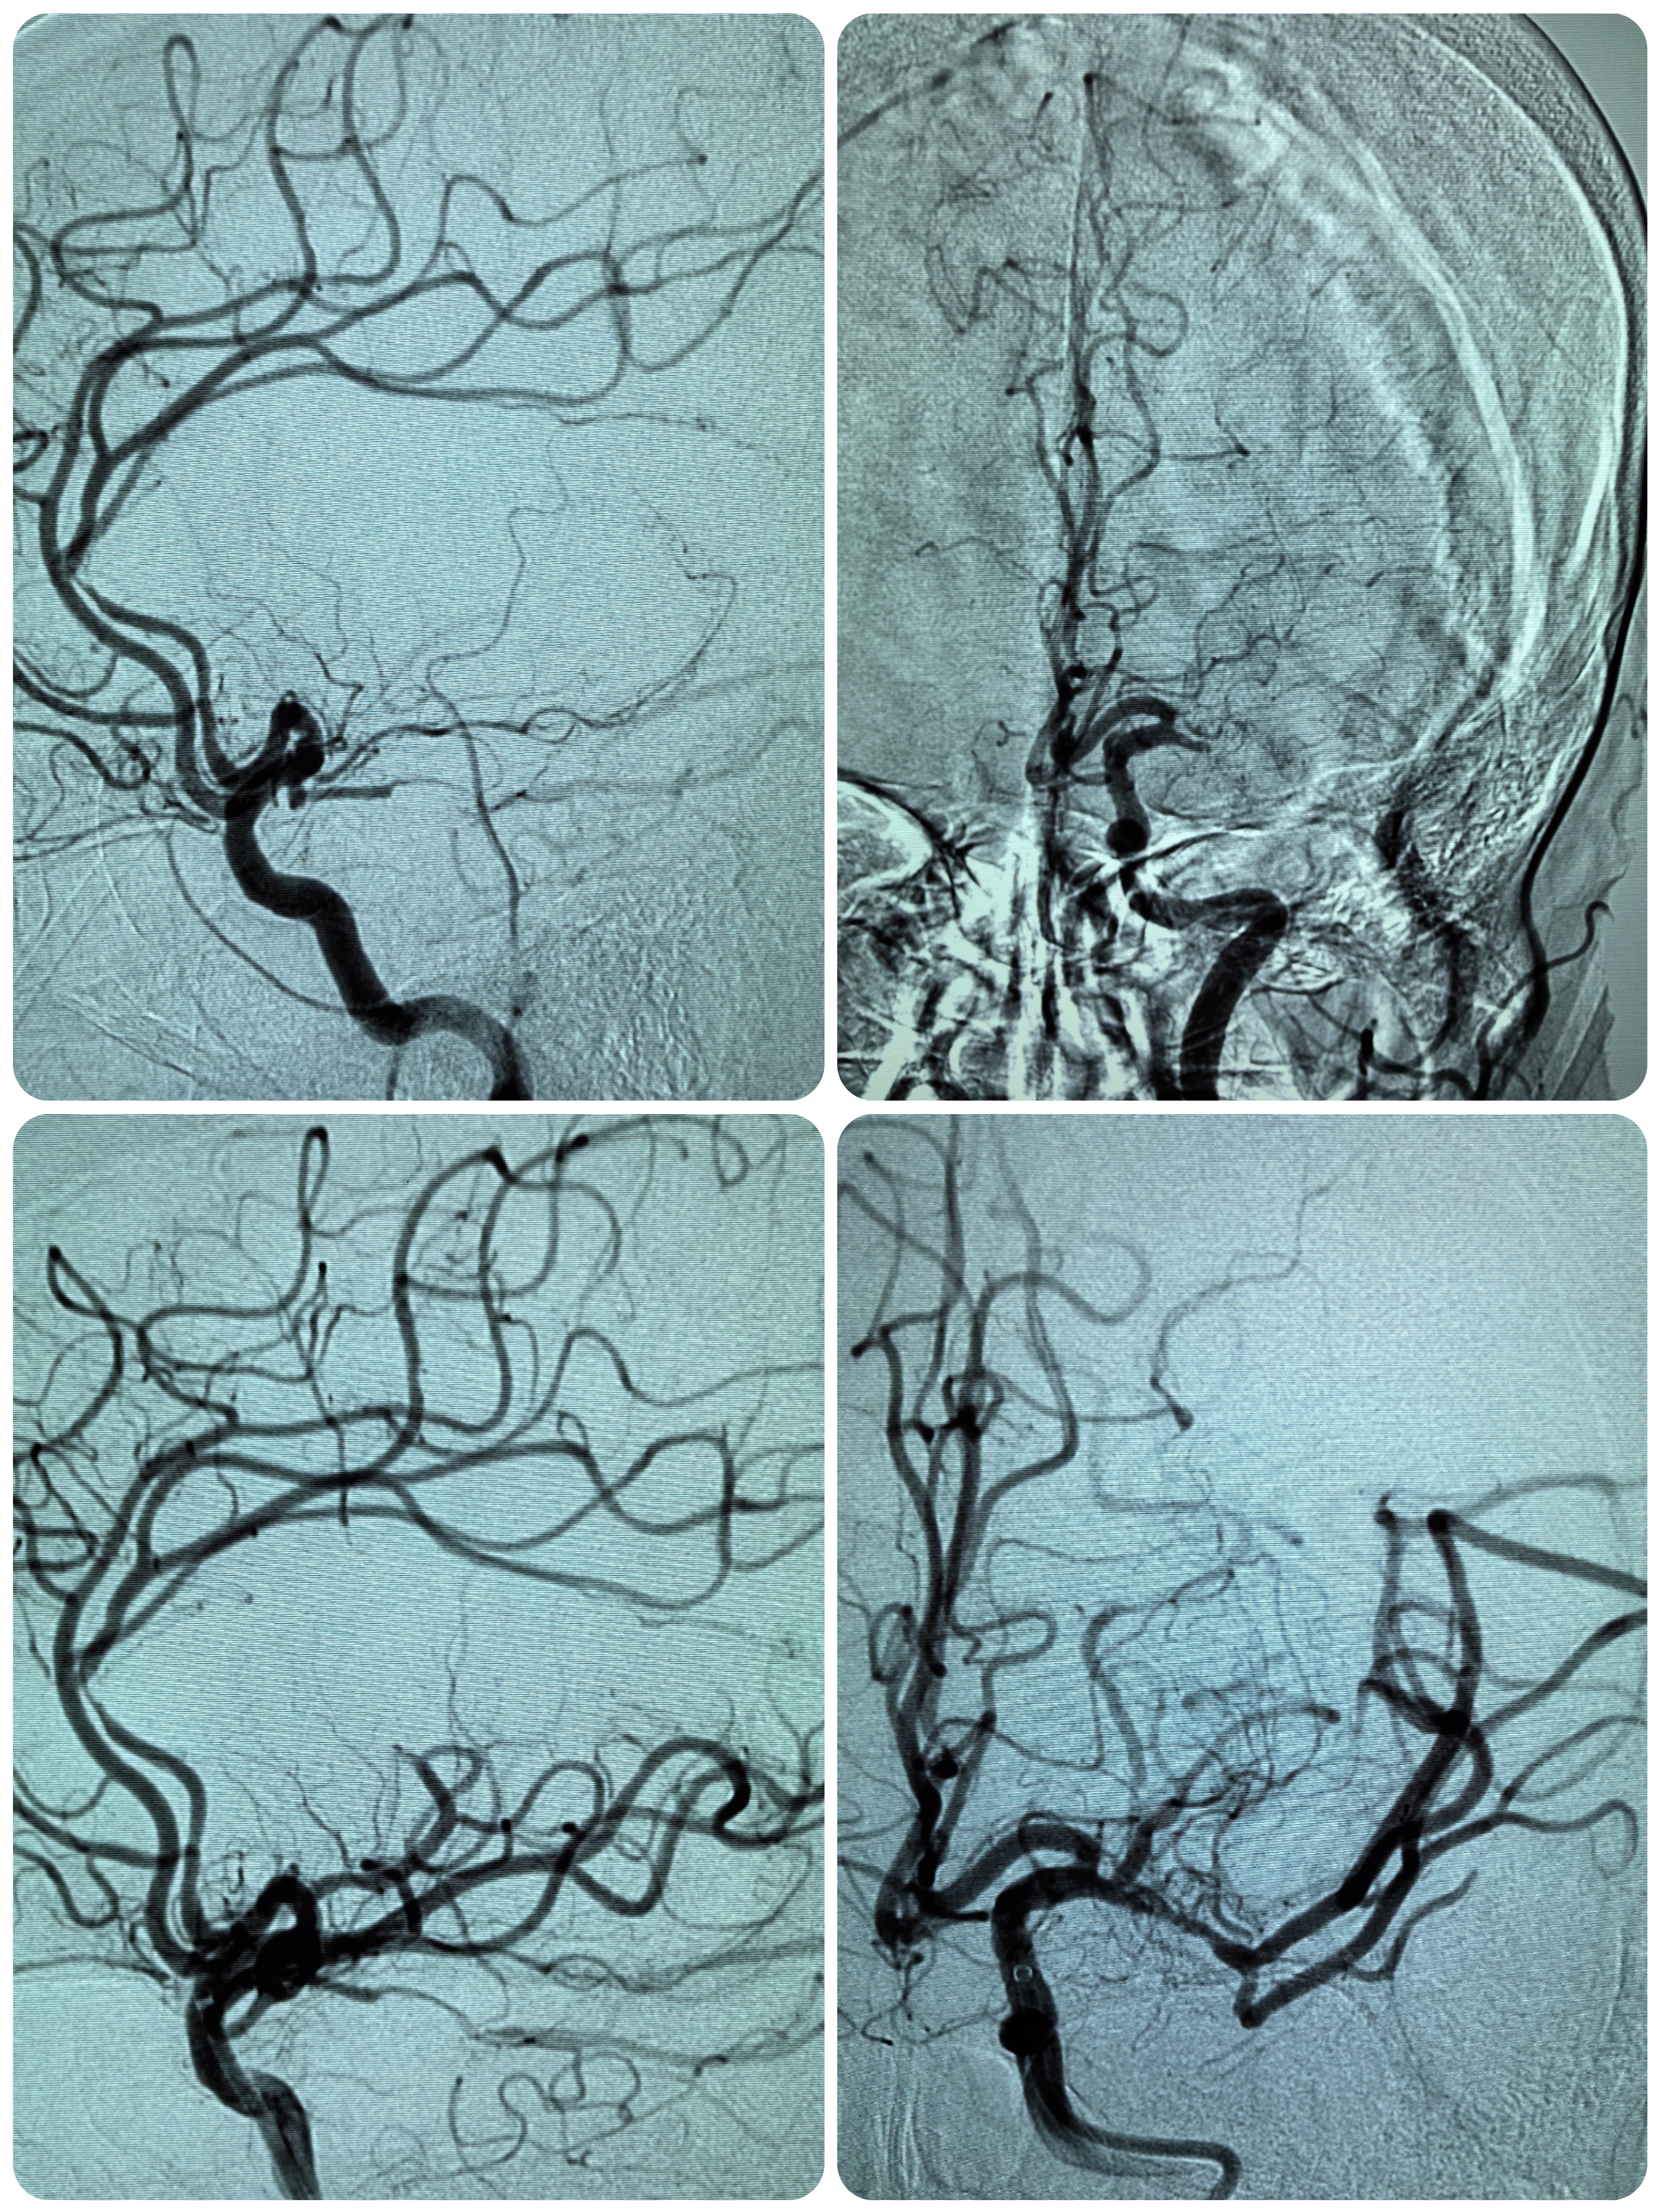

1、本例患者老年女性,系骨科术后次日醒后卒中,经核磁评估提示左侧大脑中动脉闭塞,系责任血管,患者心电图示房颤,考虑心源性栓塞可能性大。

2、本例患者SWIM技术取栓一次后血管再通,颅内血流通畅。